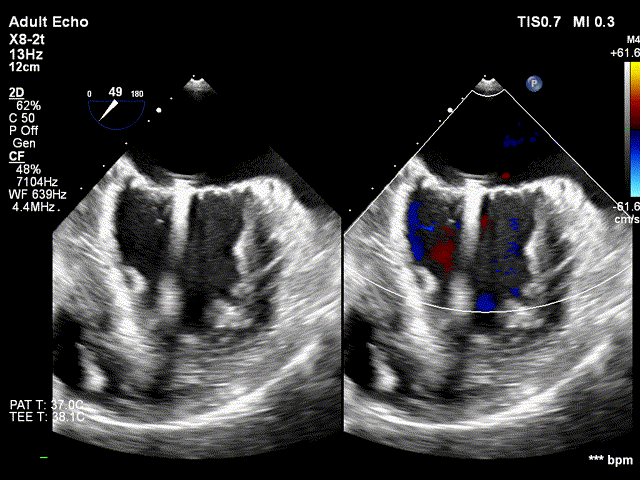

DMR:二尖瓣重度反流5+,P2区脱垂连枷,AP:38mm,MVA:6cm²,反流宽度14.2mm,反流2区,P2区脱垂范围14mm,连枷间距4mm,脱垂高度6.6mm,瓣环直径37mm。

患者为原发性二尖瓣反流(DMR),基线期二尖瓣反流程度5+。反流主要位于2区,脱垂宽度约14mm,MVA约6cm²。为保证反流程度有效降低,需要在2区夹合器方向指向主动脉与二尖瓣闭合线垂直进行夹合。

全麻后,首先在心前区的肋间切开3-4CM小切口,暴露心脏的心尖位置,心尖穿刺后进入导丝,利用导丝交换导管鞘完成通路建立。将系统送入左心房,顺利到达二尖瓣病变区域。在经食道超声引导下,术者通过反复评估二尖瓣反流位置、抓捕位置、反流程度,在2区主动脉瓣与二尖瓣闭合线垂直进行巧妙夹合,最终植入一枚ValveClamp®MVC-Ⅲf夹。超声评估夹子固定良好,组织桥完整,无葫芦征,位置、轴向均符合预期。患者术后反流程度从大量转至少量,手术取得圆满成功。患者恢复良好,已经顺利出院。